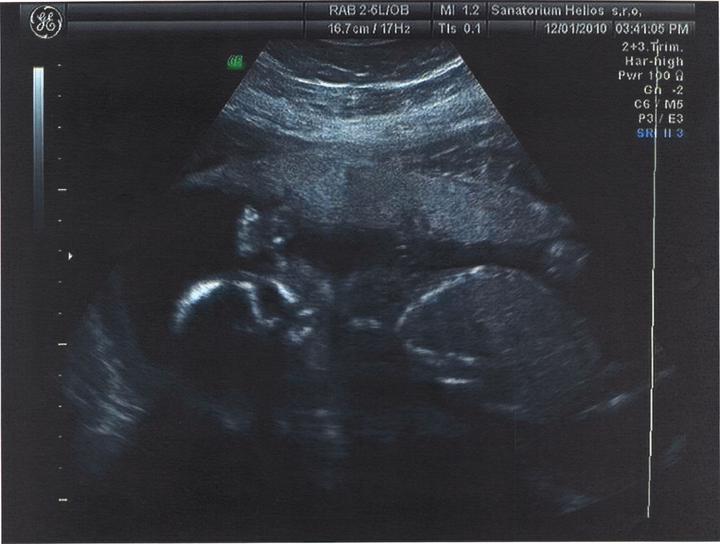

Jsme zpátky z dovolené, prcek v bříšku ani moc nezlobil🙂